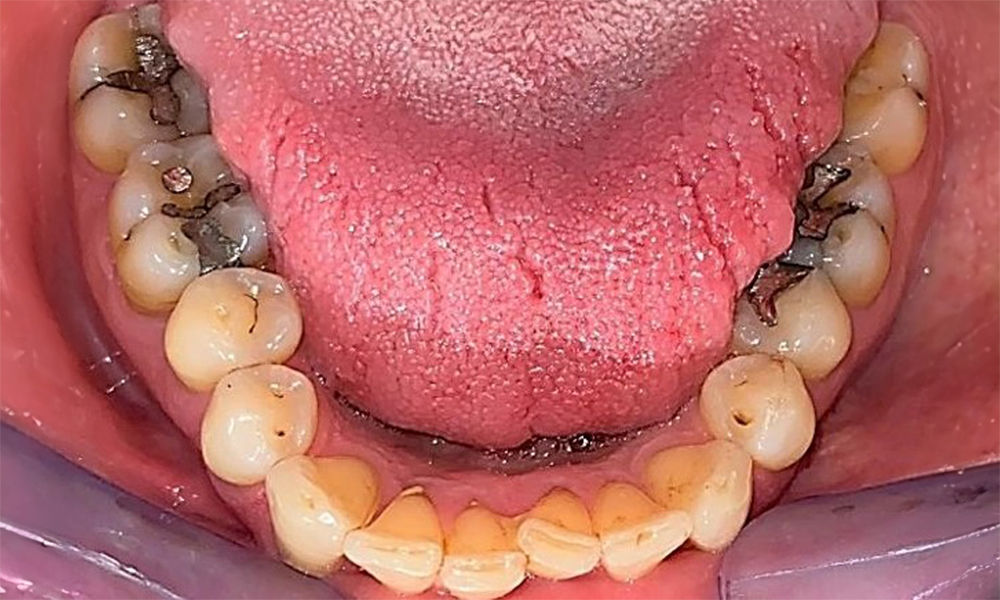

Okklusalansicht Unterkiefer zur Darstellung der vorhandenen Restaurationen. © Dr. R. Krapf

Abb. 6 Okklusalansicht Unterkiefer zur Darstellung der vorhandenen Restaurationen. © Dr. R. Krapf